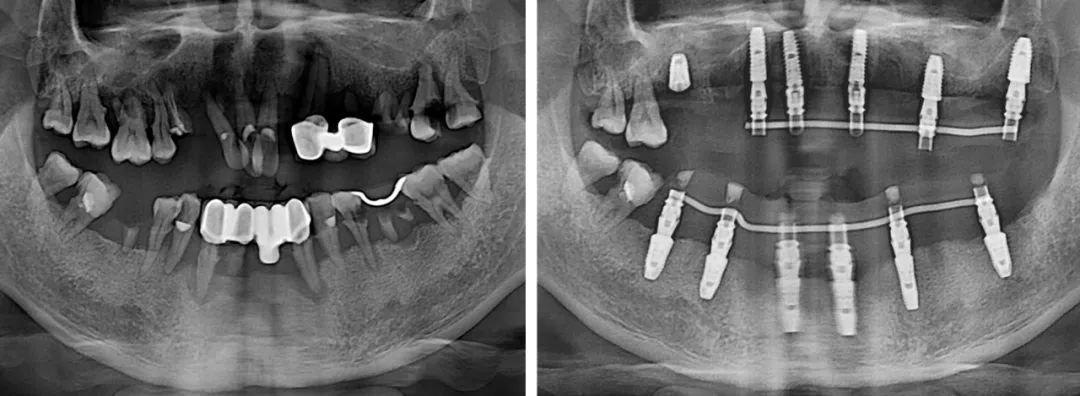

短短几年,刘今朝已完成种植修复治疗上千例,成长速度比绝大多数同龄医生更快。工作以来,他已多次公派参加专业培训和学术会议,同时,也完成了从常规种植到半口全口无牙颌种植的技术进阶。

“做种植牙,良好的咬合是最终目的。相对单颗、多颗种植,半口咬合重建难度更大。半口种植的患者往往对侧牙齿也不是特别好,种植后如何调整咬合,非常考验医生的水平。”

技术进阶,意味着难度也有了进阶,不管遇到什么样的病例,刘今朝始终牢记“修复是种植的目的”这一原则,以最终的修复效果为目标,来指导整个治疗。